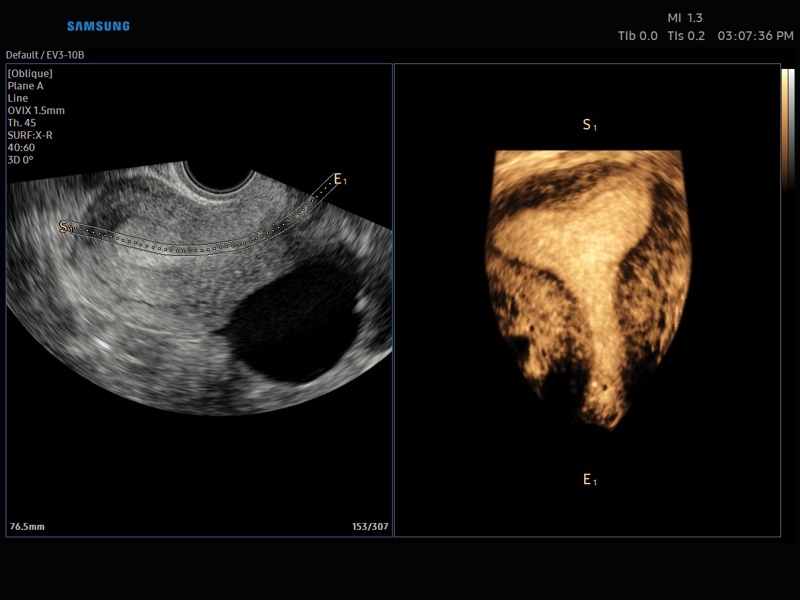

• Акушерство и гинекология

• OVIX(Oblique View eXtended) - получение фрагмента трехмерного изображения (в виде нескольких полупрозрачных сканов, последовательно наложенных один на другой) в направлении произвольного косого среза трехмерного объекта исследования.

• Модуль Realistic Vue - программа реконструкции реалистичного 3D УЗИ, при котором на объемное изображение накладывается виртуальный источник освещения. Специальный процессинговый алгоритм воспроизводит трехмерную анатомию плода с исключительной детализацией.

• МодульCrystal Vue- программа реконструкции прозрачного 3D УЗИ, которое получается при одновременном усилении внутренних и наружных структур. Применяется для визуальной оценки состояния плода и матки, помогает лучше идентифицировать мягкие ткани и кости.

• Модуль Crystal Vue Flow- программа реконструкции прозрачного 3D УЗИ, которое получается при одновременном усилении внутренних и наружных структур. Применяется для визуальной оценки состояния плода и матки, помогает лучше идентифицировать мягкие ткани и кости. Так же визуализирует объемный кровоток.

• СистемаLive 3D- трехмерное сканирование объемными датчиками в реальном масштабе времени (4D).